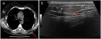

Imagiological features of the tumor: A, High-resolution thoracic computed tomography revealing a large, low-density, subcutaneous nodule in the left dorsal region (red arrow); B, Ultrasound revealing a well-defined, slightly hyperechoic, subcutaneous mass in the left dorsal region (red arrow).

A high-resolution thoracic computed tomography performed one year before, in the context of an episode of asthma exacerbation, had revealed a large, low-density, subcutaneous nodularity in the referred topography (Fig. 1A). Also, an ultrasound-guided core needle biopsy (Fig. 1B)of this well-defined, slightly hyperechoic, subcutaneous mass identified a neoplasm of globular cells, some with multi-vacuolated cytoplasm and others with granular, eosinophilic cytoplasm, without nuclear atypia.